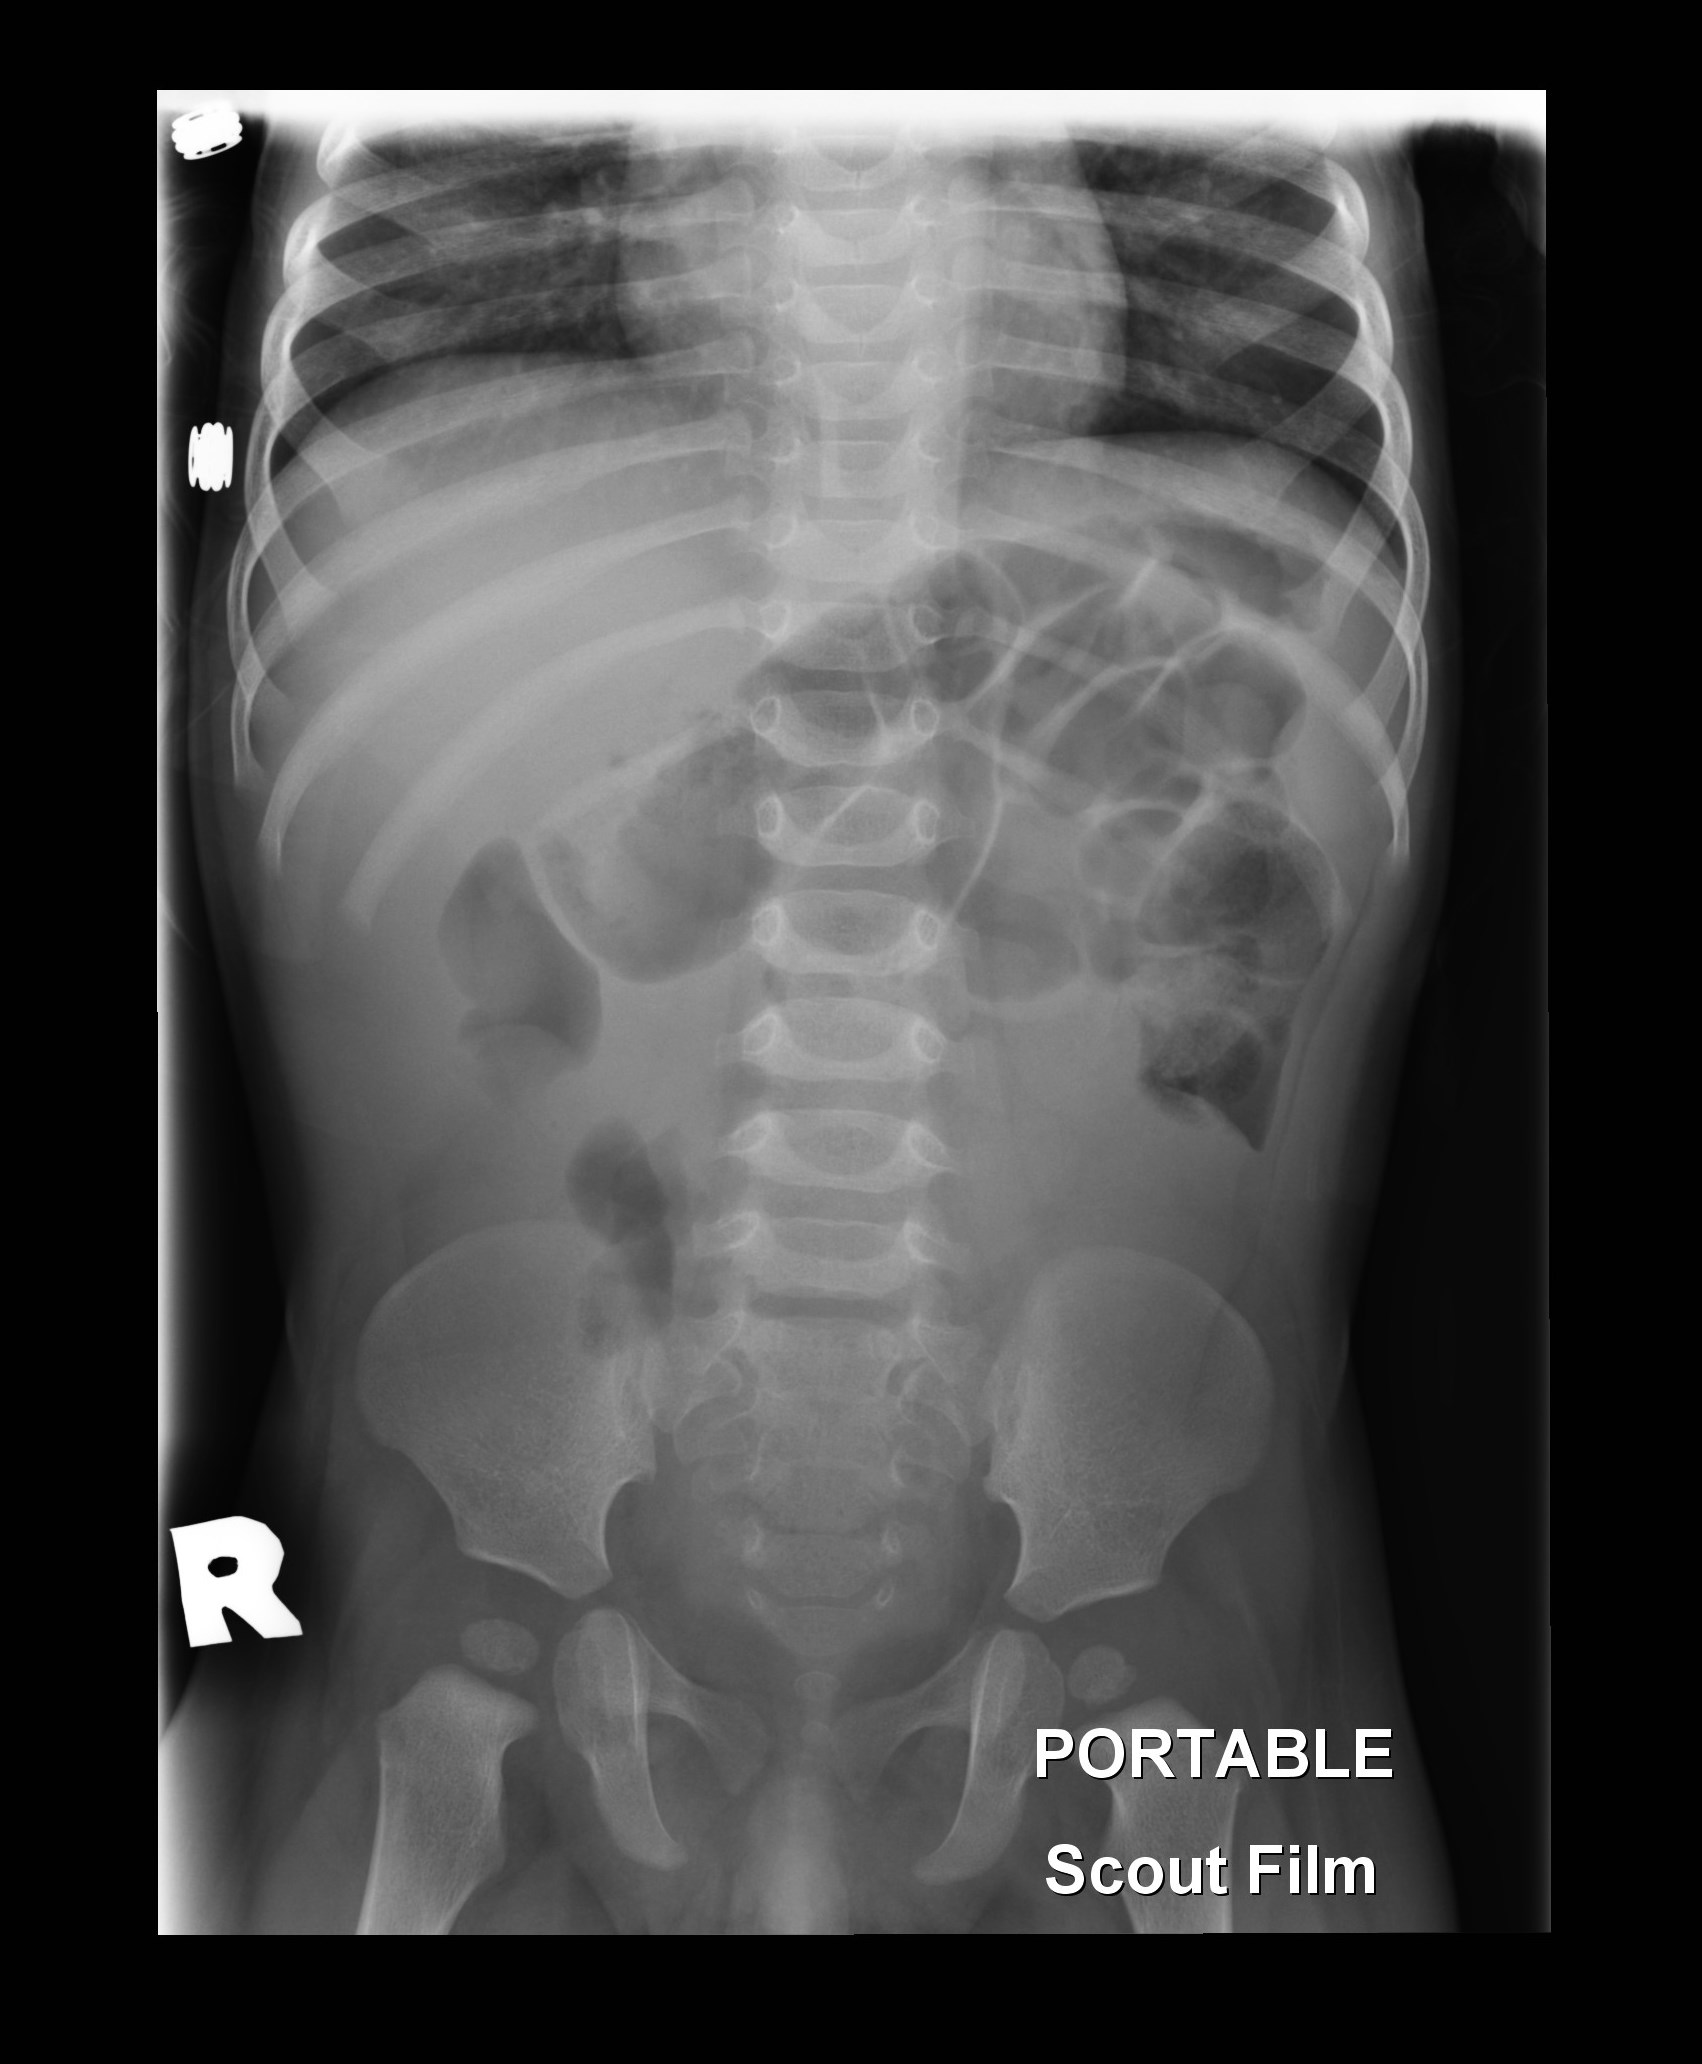

a 10-year-old boy who presents with his third episode of acute onset abdominal pain.

The only other information you are provided are pictures of the boy's face and hands

an an abdominal x-ray taken during the last episode of abdominal pain (see below).

Intussusception of the bowel is a life threating condition which requires immediate

diagnosis and treatment. The sensitivity of radiography in confirming the diagnosis

is 48% whereas the sensitivity of abdominal ultrasound, the procedure of choice, is

97.9% with a specificity of 97.8%.